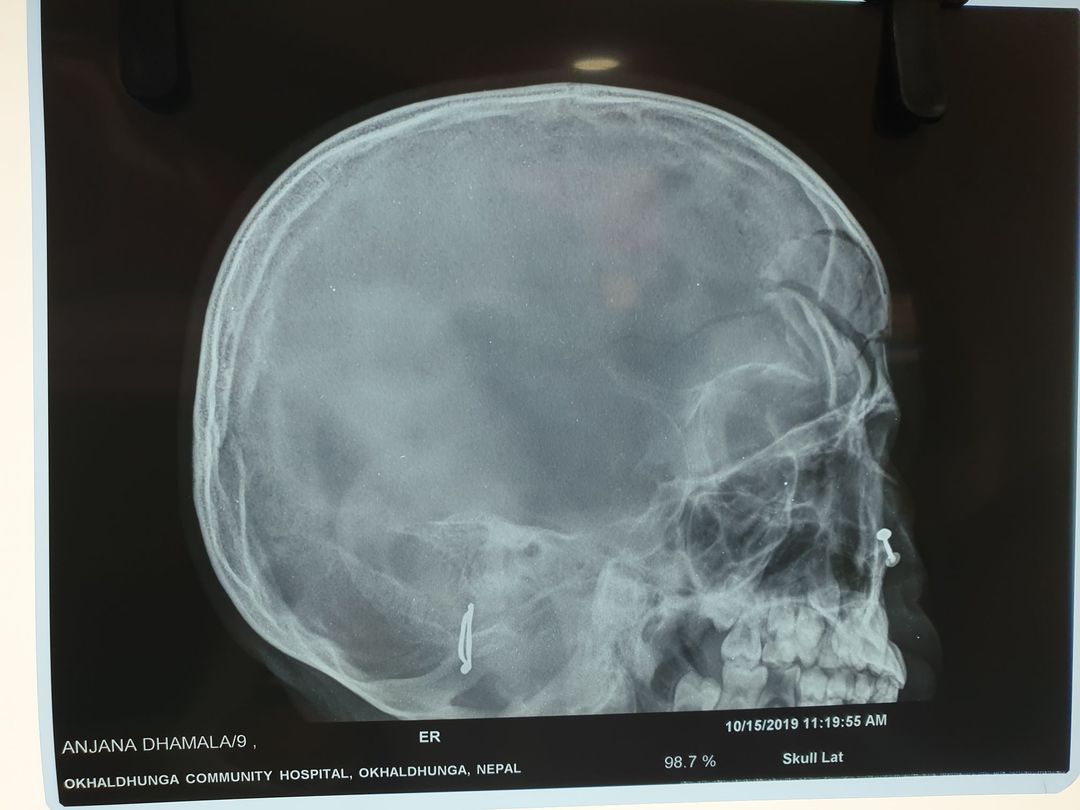

Case study

Study

Case

Fracture